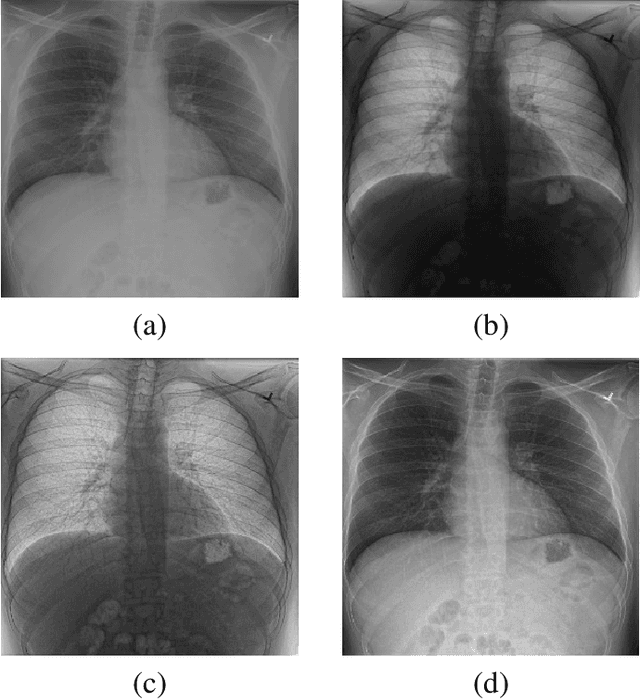

Abstract:X-ray imaging is a fundamental clinical tool for screening and diagnosing various diseases. However, the spatial resolution of radiographs is often limited, making it challenging to diagnose small image details and leading to difficulties in identifying vertebrae anomalies at an early stage in chest radiographs. To address this limitation, we propose a novel and robust approach to significantly improve the quality of X-ray images by iteratively training a deep neural network. Our framework includes an embedded internal guidance layer that enhances the fine structures of spinal vertebrae in chest X-ray images through fully unsupervised training, utilizing an iterative procedure that employs the same network architecture in each enhancement phase. Additionally, we have designed an optimized loss function that accurately identifies object boundaries and enhances spinal features, thereby further enhancing the quality of the images. Experimental results demonstrate that our proposed method surpasses existing detail enhancement methods in terms of BRISQUE scores, and is comparable in terms of LPC-SI. Furthermore, our approach exhibits superior performance in restoring hidden fine structures, as evidenced by our qualitative results. This innovative approach has the potential to significantly enhance the diagnostic accuracy and early detection of diseases, making it a promising advancement in X-ray imaging technology.